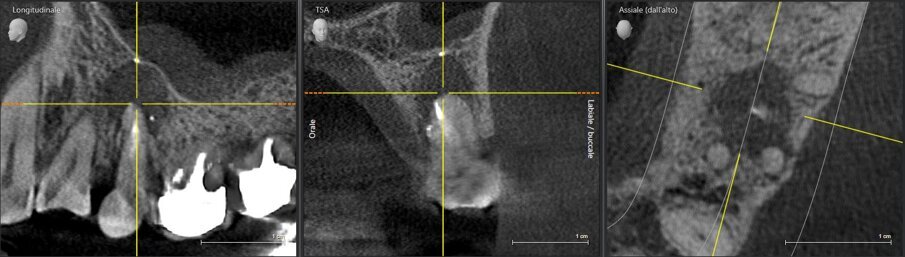

Si effettua prima una lastra endorale e in seguito una CBCT dell’elemento per valutare le possibilità di ritrattamento endodontico e la morfologia del difetto osseo, dalle quali si evince come le corticali appaiono essere mantenute ma che la porzione midollare dell’osso alveolare risulti completamente riassorbita. Gli elementi 26 e 27 presentano terapie endodontiche incongrue ma essendo asintomatici e privi di lesioni periapicali si sceglie insieme alla paziente di tenerli monitorati (Figg. 4, 5).